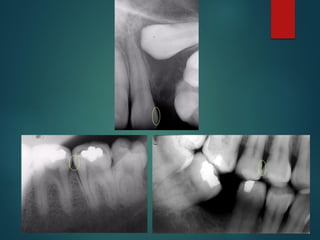

Incipiente de esmalte

De esmalte

Dentinaria superficial

Dentinaria profunda

Sobreproyectada en cámara pulpar

Penetrante

Clasificación Radiográfica

De Las Caries

 Incipiente de esmalte

 De esmalte

 Dentinaria superficial

 Dentinaria profunda

 Sobreproyectada en cámara

pulpar

 Penetrante